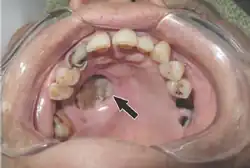

Should the fungus deposit in the nose or sinus and extend to brain, symptoms and signs may include one-sided face pain or headache.[7] There can be numbness, fever, loss of smell, a blocked nose or runny nose.[7] The person may appear to have sinusitis.[23] The face may look swollen on one side, with rapidly progressing "black lesions" across the nose or upper inside of mouth. One eye may look swollen and bulging, and vision may be blurred.[5][23][24]

Tissue destruction of inside upper mouth -